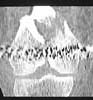

A male 31 y.o. addmitted to our unit today with the subject (see attachment). Injured in a car accident 1 month ago, since that he has been at bed traction. Other fractures are minor - undisplaced pubic rami and distal ulna.

What is your opinion about optimal program here? Is closed nailing a good option here? Articular part of condyles looks fine, but the lateral one seems to be too small and comminuted. Or external fixation as definitive method? Or open the fracture at least distally, fix condyles then nail?

Of course the only radiograms both the view of the femur (AP and LL) are not enough in order to assess the condyles. So I think a TAC of the knee could be useful.

A CT and knee xrays would help identify lateral condyle comminution and/or a "hoffa fragment" of the posterior condyle. I am concerned that the lateral cortex is not sufficient to give purchase for a retrograde IMN. blocking screws could improve this as a possibility.